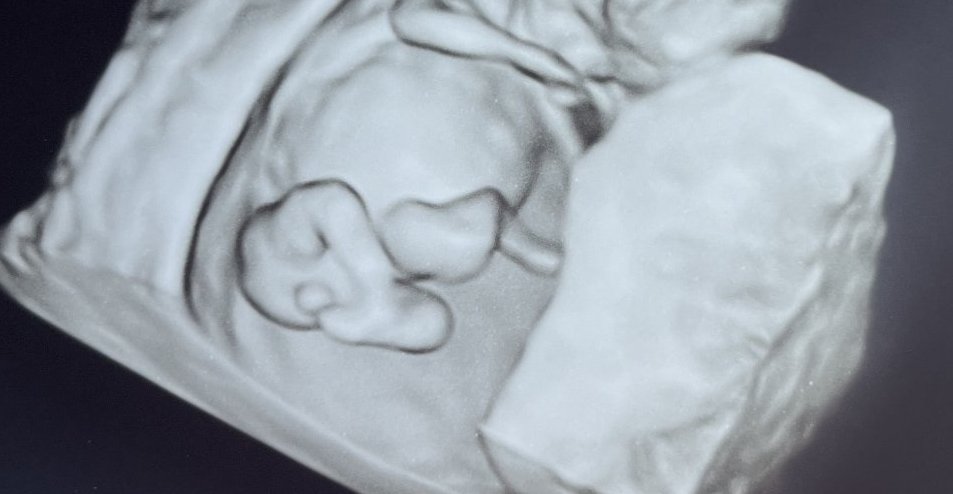

Здравейте тази снимка отговаря ли за 6 г седмица

Каза че съм в 6 седмица нищо повече ?

Да!